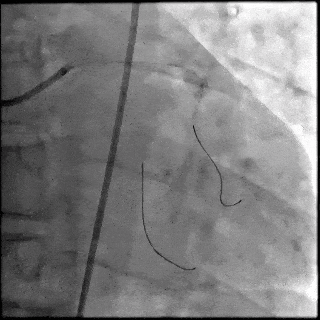

5月28日8:00,葛均波院士团队在中山医院16号楼16楼中伟厅成功连线喀什二院导管室,沪喀远程手术正式开始。8:35,新疆喀什二院导管室内股动脉入路通路建立后,行左右冠脉造影示左前降支中段存在85%的严重狭窄,狭窄位于血管分叉路口且紧邻心肌桥;且左回旋支中段近乎闭塞,血管细窄且迂曲,病变弥漫。8:59,葛院士于上海操控血管介入机器人主端,将指引导管送至左冠脉开口,并操控主支导丝和分支血管保护导丝通过狭窄病变,后送至前降支和对角支血管远端以建立轨道,同时利用介入机器人的微速调整功能避开心肌桥,以亚毫米级精准定位释放1枚支架。在成功处理患者左前降支病变后,葛院士通过搓捻机械操纵杆,远程精细调整导丝“进攻”方向,顺利通过左回旋支次全闭塞病变。因血管相对细小且病变弥漫,葛院士决定采用单纯球囊扩张术处理,即刻造影提示几乎无残余狭窄,避免了额外的支架植入。10:10,撤出所有导丝及导管,手术顺利结束。

【DSA图2.前降支支架释放】